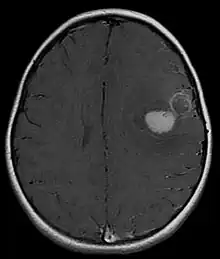

The approach to management of a CNS PNET is first to obtain detailed imaging through MRI, as well as additional scans of the patient's body (X-ray, CT, PET, even bone marrow biopsies) to look for metastasis or other associated malignancies. The tumor will then need to be biopsied to confirm the diagnosis. After the diagnosis of a CNS PNET is confirmed, management includes neoadjuvant chemotherapy and radiation (to reduce tumor size burden), complete surgical resection with confirmed negative margins, and/or additional adjuvant post-surgical chemotherapy. CNS PNET is aggressive and must be managed as so. Palliative care services should also become involved in the patient's care team when the diagnosis is made. [6]